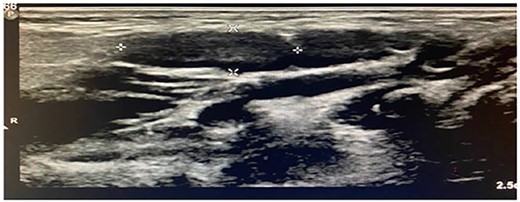

Imaging examination of the patient was done by performing CT with contrast and US. US Doppler showed a right dilated internal jugular vein during coughing and the valsalva maneuver (Fig. 5). CT showed a wide right internal jugular vein (Fig. 6). Both cases managed conservatively with follow-up and no surgical intervention as they did not have any complication or cosmetic concerns.